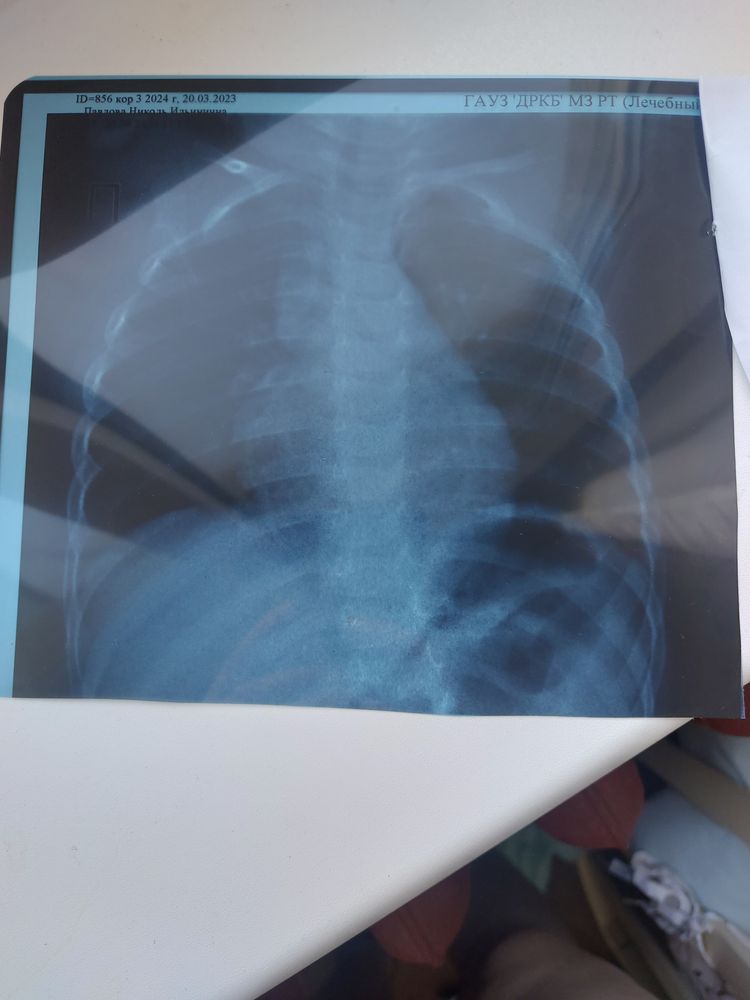

Рентген, описание

Алина, тут совсем ничего не видно по легочной ткани --- выпота нет сердце аорта правильно расположенно больше не видно ничего

Вижу сколиоз

Алина, белое это сосуды, вроде нормальные легкие, а сколиозом по шрот терапии лучше всего заниматься, ребенок маленький, а уже искривление